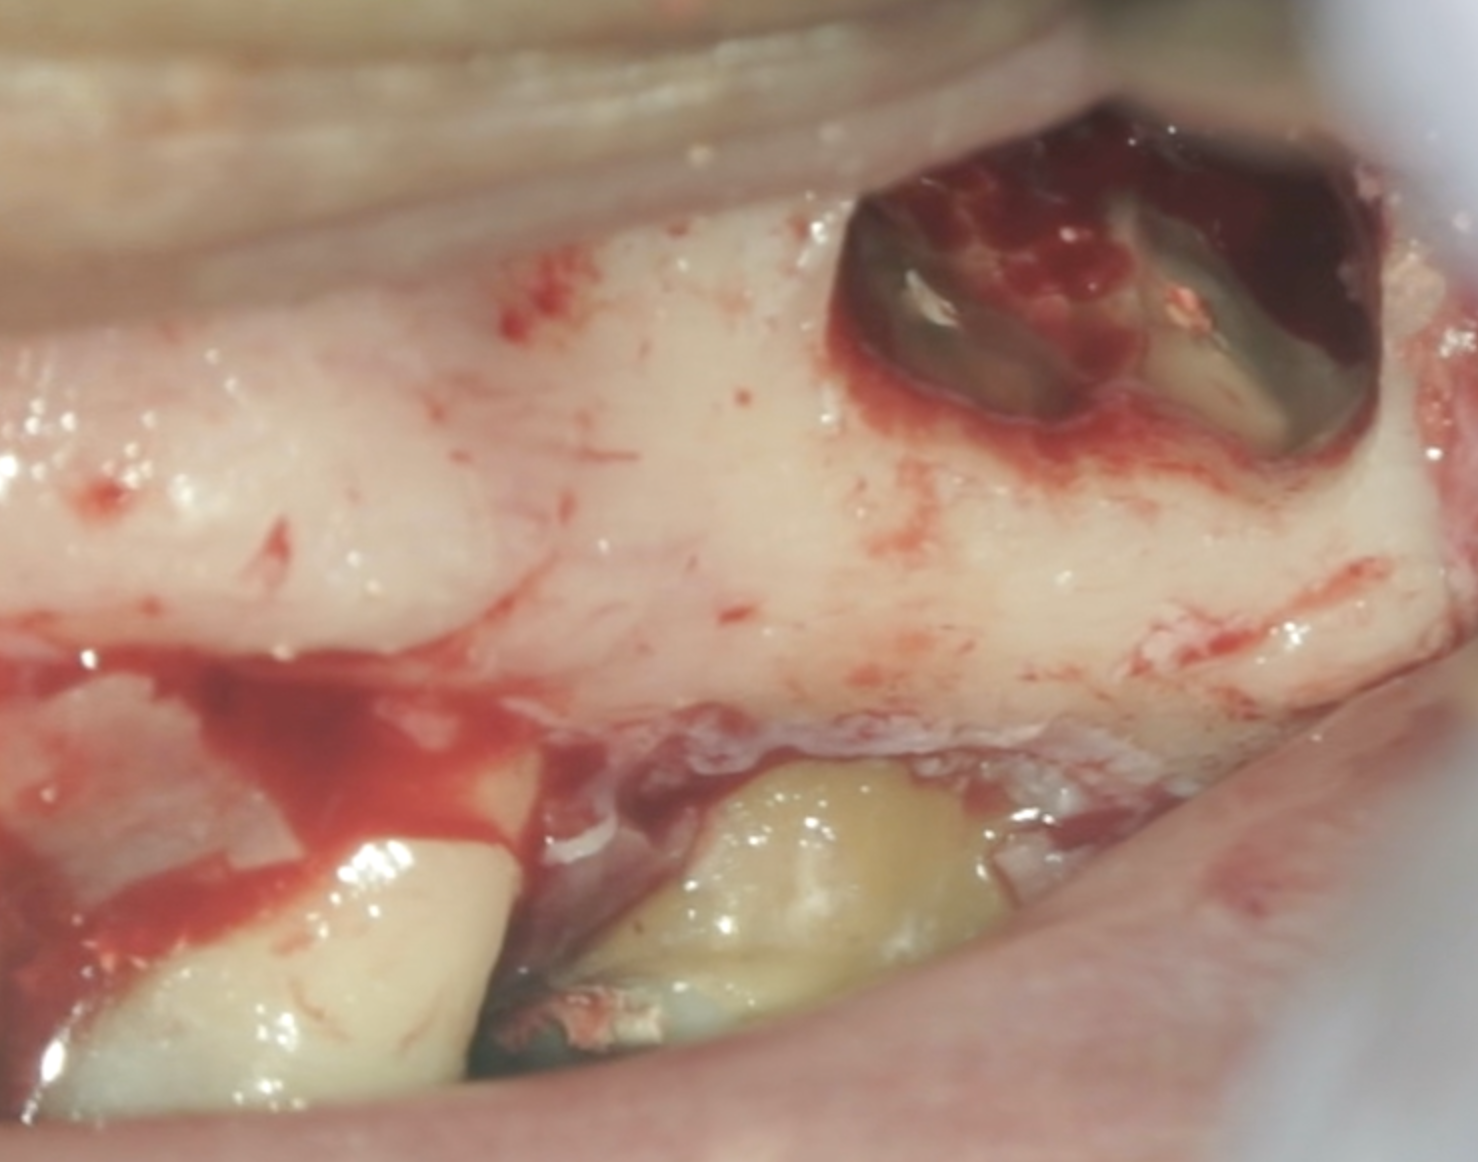

#14 MB,DB Apicoectomy→Intentional Replantation(2024.6.21)

そもそもは頬側の皮質骨はあったのだが、

抜歯時にMB,DBを短くしておこうと切断して抜歯をしようとするが…

それでも抜けない…

抜歯作業中に、私は気づかないうちにApico-marginal deffectを人為的に作成してしまっていたようだ。